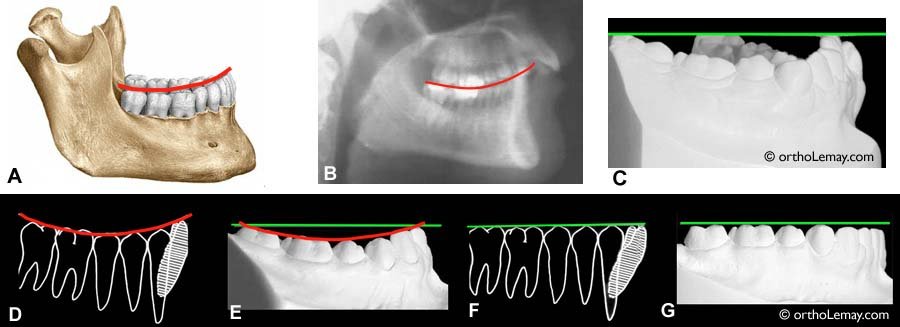

- dans le plan sagittal : orientation du plan d’occlusion. Courbe de SPEE, trajectoire condylienne et angulation cuspidienne.

- Analyse et Équilibration des secteurs postérieurs : d’abord l’arcade inférieure en rétablissant le plan d’occlusion par la méthode du drapeau de BRODRICK afin de s’en servir comme référence pour équilibrer l’arcade maxillaire.